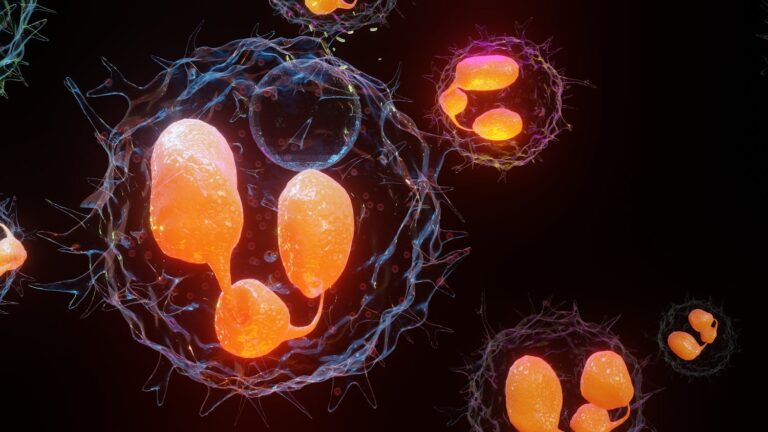

Pathologie systémique rare, la maladie à IgG4 peut toucher différents organes : les glandes salivaires, le pancréas, les voies biliaires ou encore les reins. Comment la diagnostiquer ? Quels sont les traitements ? Le point avec le Pr Nicolas Schleinitz,…